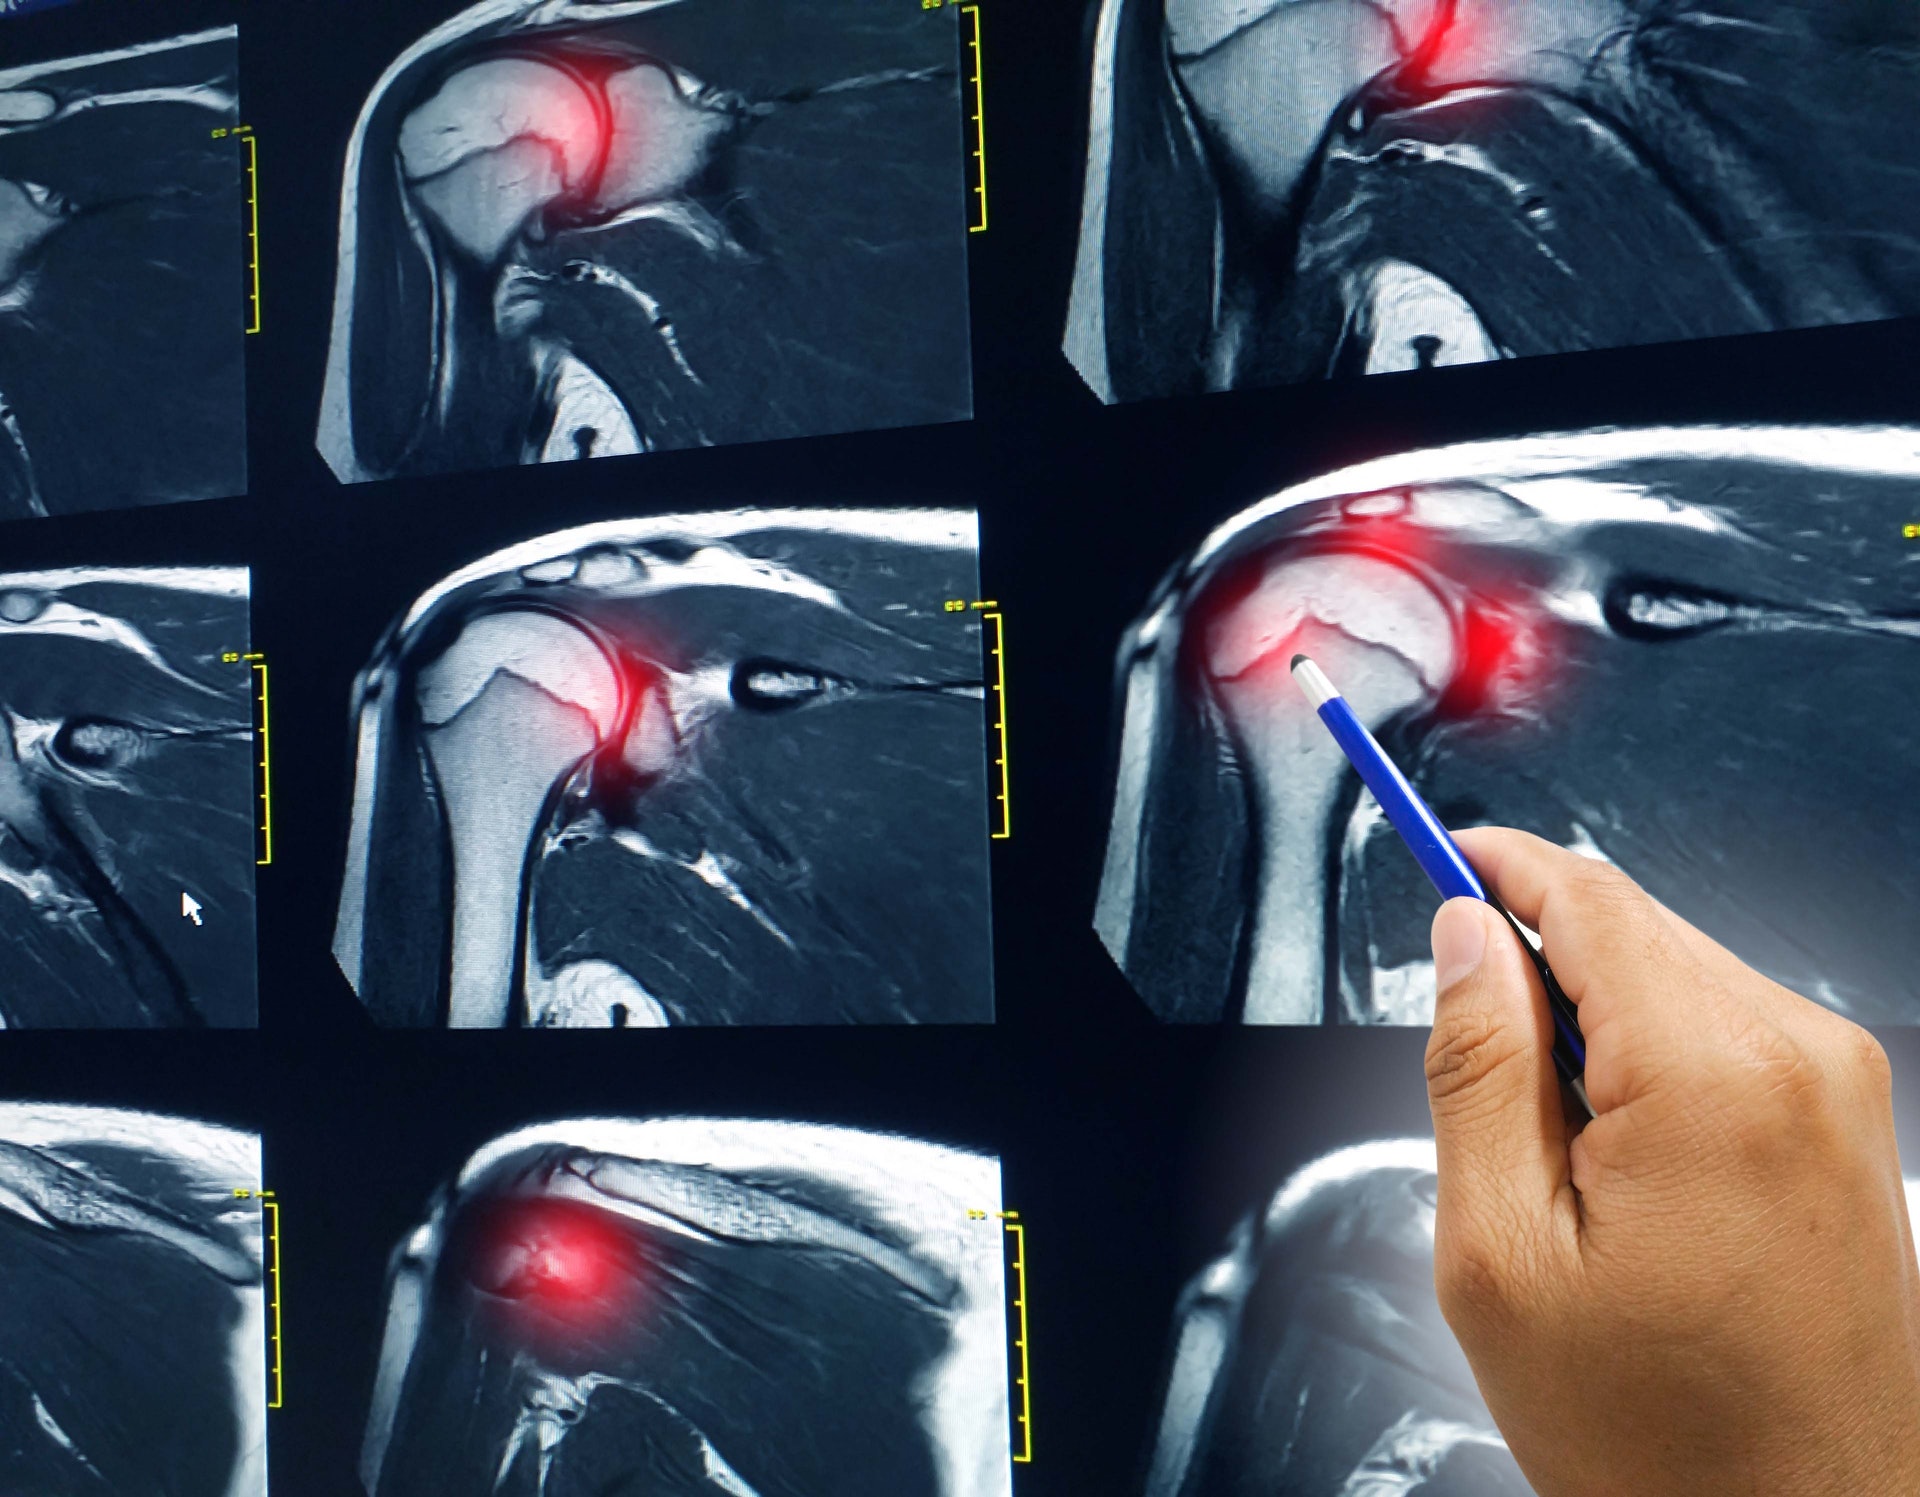

唐醫生透露,早前有年約四十多歲的花藝導師因肩膀疼痛良久來求診,雖然她尚可提起手,但活動幅度僅餘90度。安排磁力共振檢查後,首先,發現她有五十肩,其關節囊因滑膜發炎而收緊。關節囊就是包裹著肩膀關節的組織,分為纖維層及滑膜層,會分泌出關節滑液減少軟骨之間的磨擦。換言之,如發炎收緊,會影響關節活動的暢順度。

其次,該病人的旋轉肌筋腱有部分撕裂。唐醫生解釋:「肩關節有點像髖關節,是球窩關節。手臂骨和肩胛骨的接觸面其實很小,能活動到這麼大的幅度,主要是靠旋轉肌。旋轉肌就像肩袖一樣包圍住關節,可協調肩部做出各種旋轉、前舉或外展等動作。」

唐醫生又發現,該病人的肩胛骨有骨刺增生情況,估計是其關節因退化或勞損令軟骨變薄,最後出現骨與骨碰撞情況,形成骨刺。肩關節空間收窄,活動時骨刺易磨擦到旋轉肌筋腱,形成肩關節夾擠症候群。